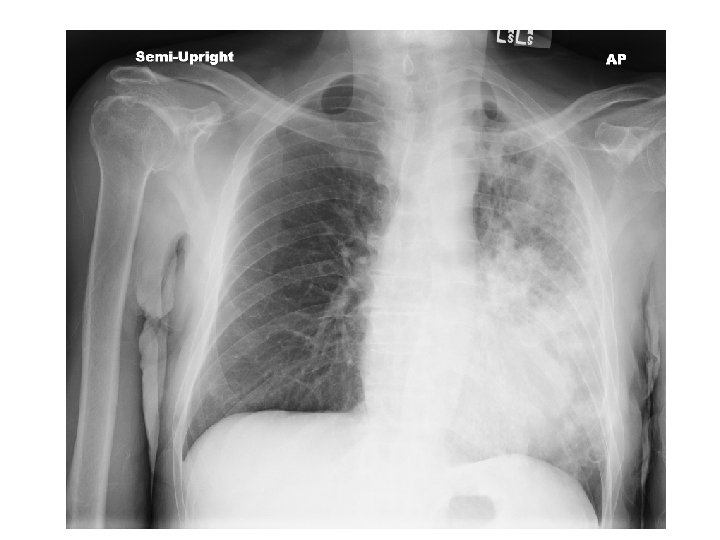

ER work-up • Abdominal XR = No obstruction/ air fluid level Atelectasis with central bronchial obstruction

CT Chest • Multiple cavitary lesions • Largest left lung apex 3. 8 x 4. 7 cm with nodular thickened wall • Smaller cavitary lesions in L lung base • R lung: smaller areas of ground-glass opacities with areas of tree in bud appearance.

Chest radiography • Active disease: upper lobe infiltration/ cavity/ effusion • Healed: nodules, fibrotic scars, calcified granulomas or basal pleural effusion • Normal in latent TB • HIV: infiltrate in any lung zone, mediastinal or hilar LAD, normal